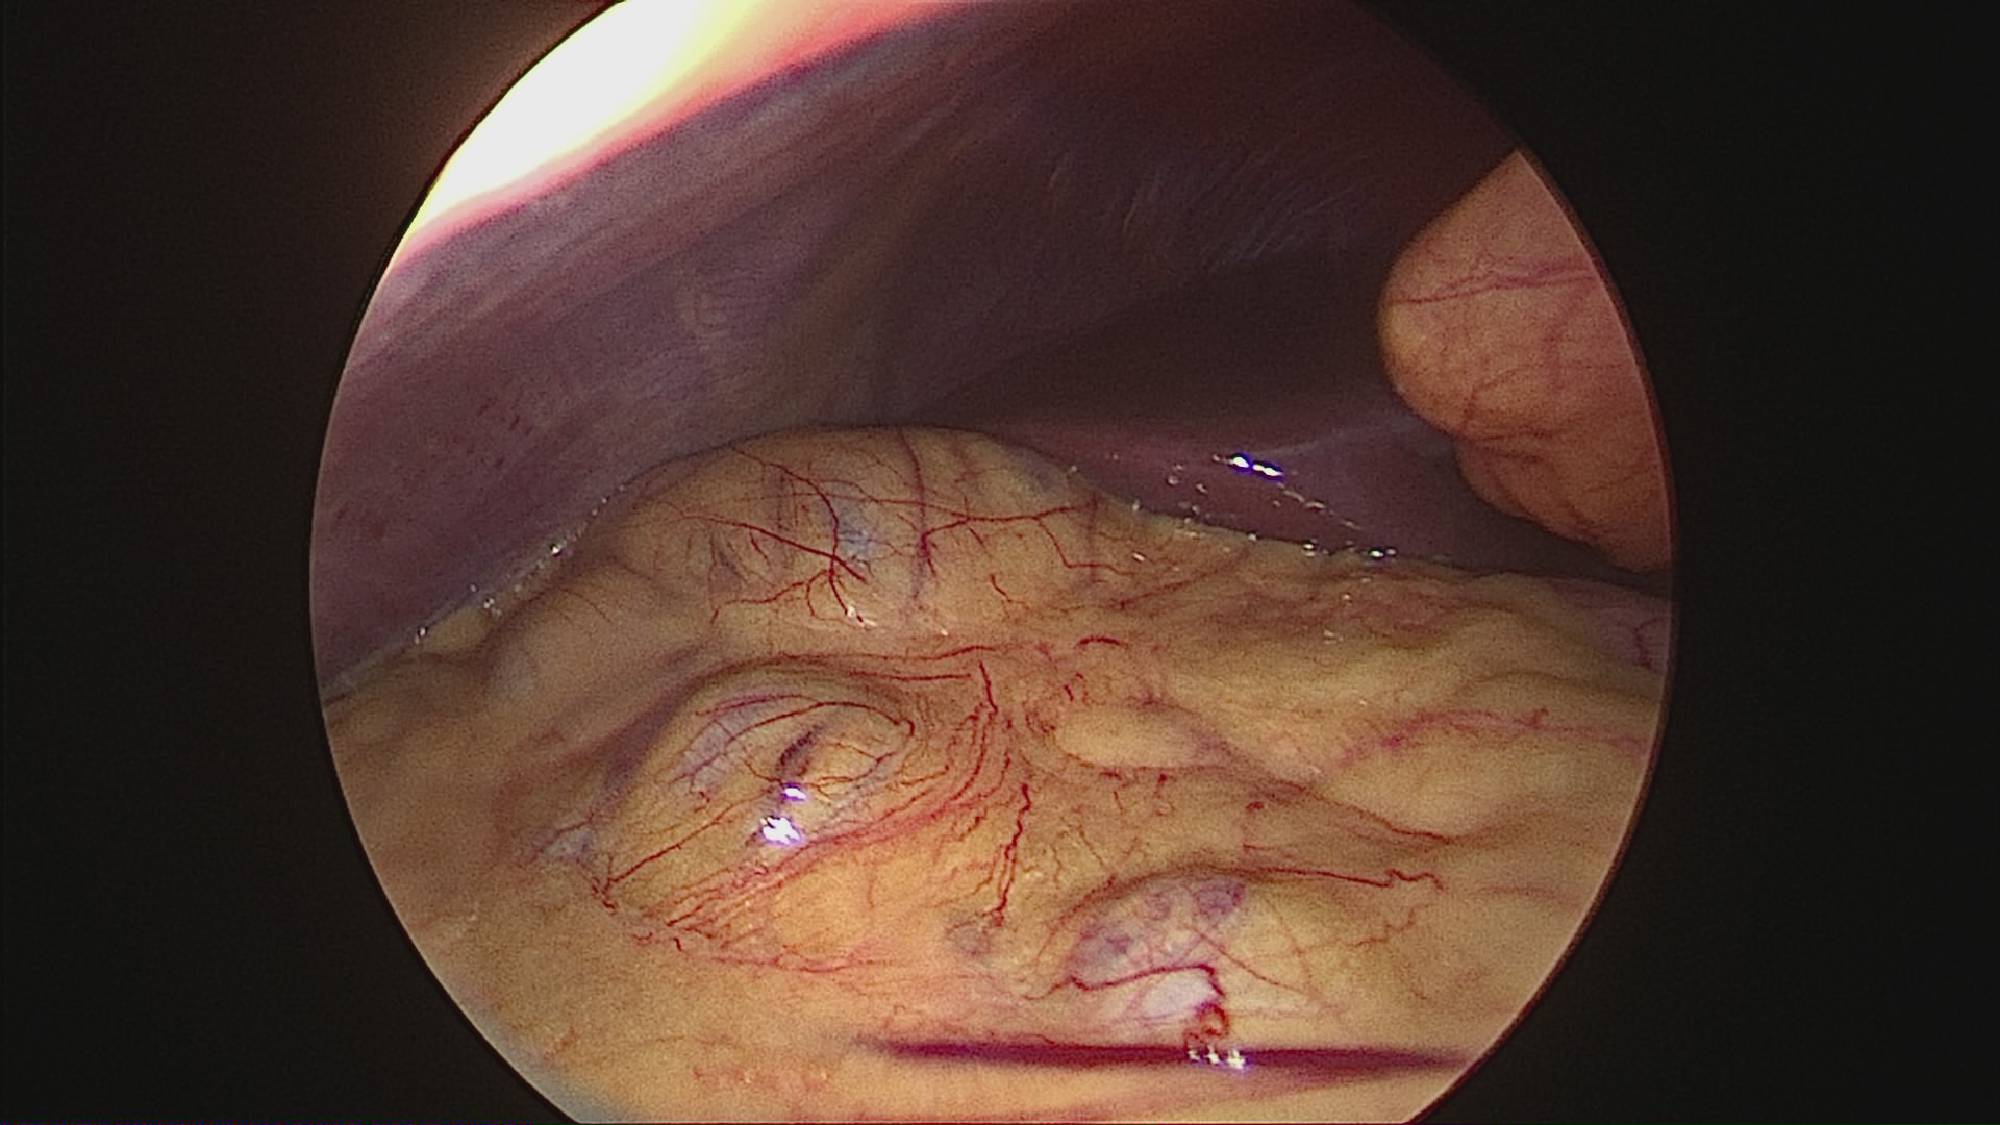

Gastrectomia longitudinală (gastric sleeve) este o intervenție care produce scăderea în greutate prin două mecanisme: restrictiv (îndepărtează o mare parte din stomac lăsând un rezervor de 80-120 ml) și hormonal (prin extirparea fundului gastric se reduce semnificativ secreția hormonului foamei, grelina).

Operația ”de micșorare a stomacului” se realizează miniminvaziv (laparoscopic) și constă în îndepărtarea marii curburi gastrice cu păstrarea antrului gastric și a micii curburi sub forma unui tub calibrat pe o sondă.